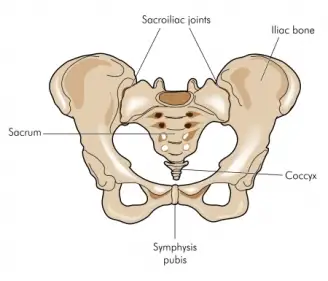

The sacroiliac joint (SI joint) is a crucial connection point between the sacrum (the triangular bone at the base of your spine) and the ilium (the uppermost bone of your pelvis). When this joint becomes inflamed or irritated, it can lead to intense lower back pain. Sacroiliac joint pain can be caused by various factors, including injury, pregnancy, or simply wear and tear over time.

The sacroiliac joints sit between the sacrum and the iliac bones in the lower back where the spine meets the pelvis. Alterations in function of the sacroiliac joints are a common cause of lower back pain.